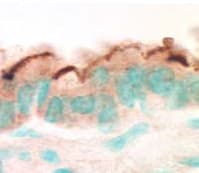

Rabbit Polyclonal EBP50/NHERF-1 antibody. Suitable for ICC, IP, WB, IHC-P, IHC-Fr and reacts with Human, Mouse, Rat, Dog samples. Cited in 44 publications. Immunogen corresponding to Recombinant Fragment Protein within Human SLC9A3R1 aa 250-350.

Applications ICC, IHC-Fr, IHC-P, IP, WB

Species Reactivity Dog, Human, Mouse, Rat